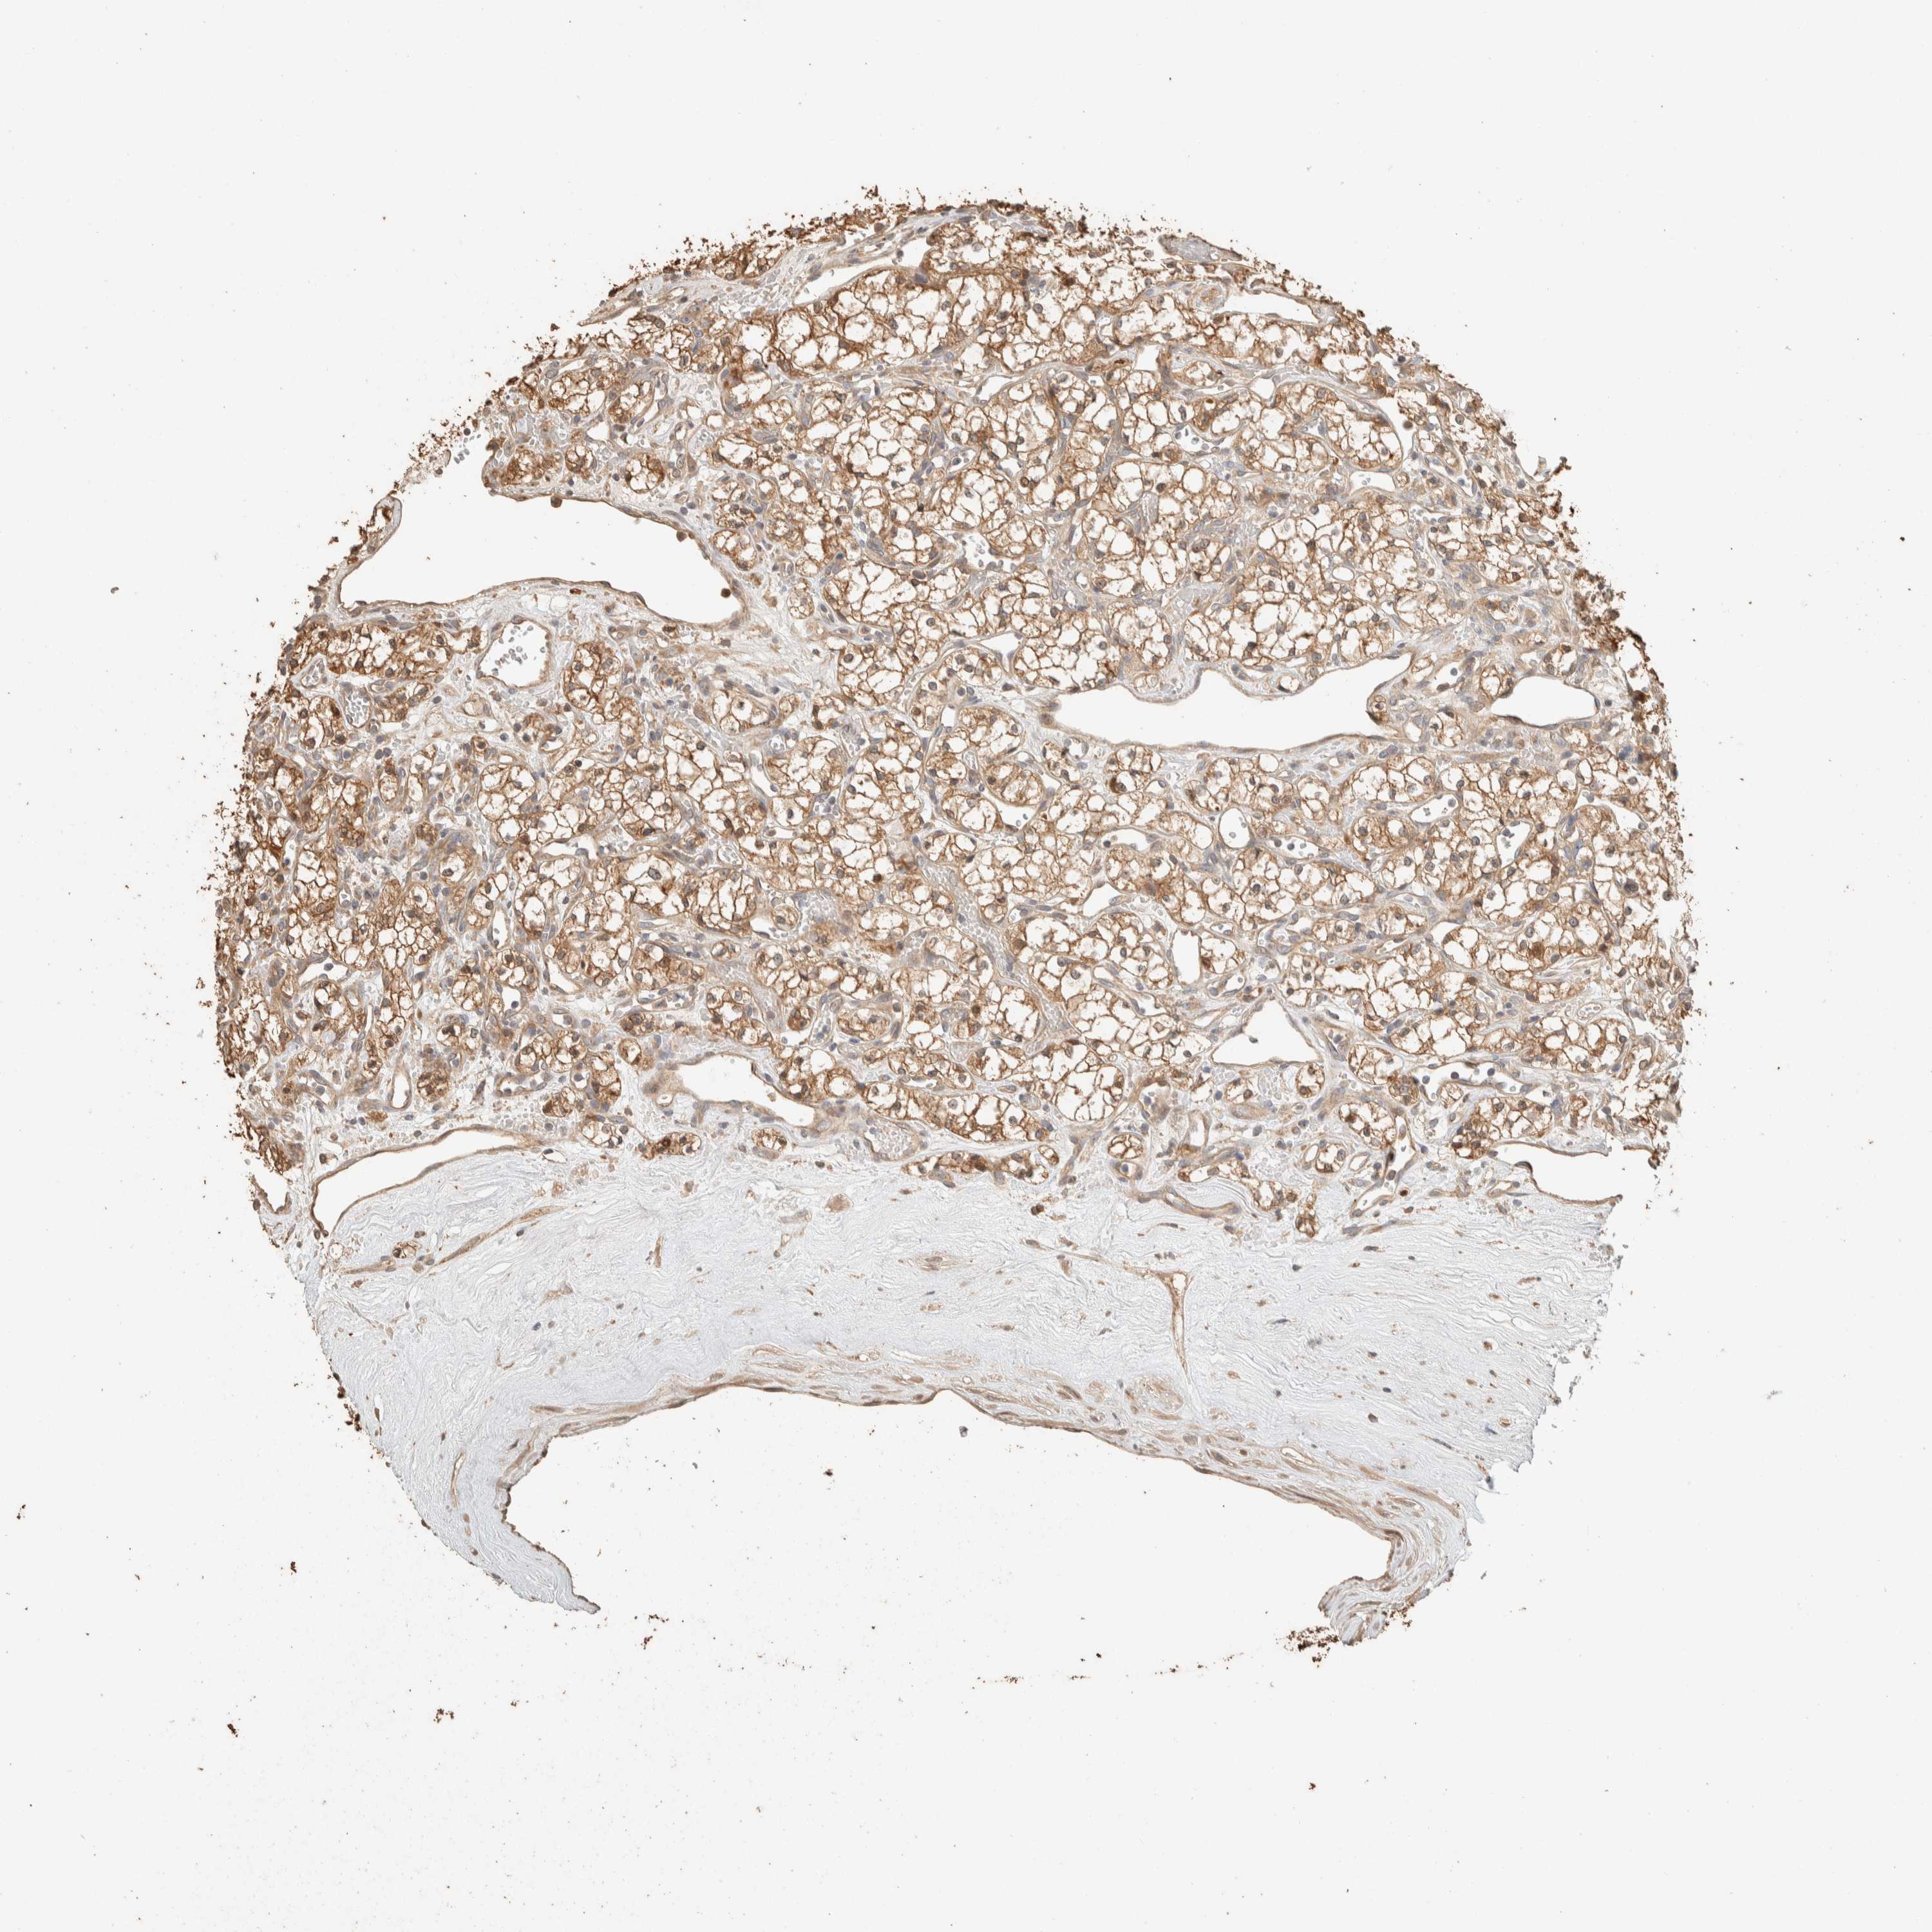

TCGA RNA samplesi

RNA-seq data is reported as average FPKM (number Fragments Per Kilobase of exon per Million reads), generated by the The Cancer Genome Atlas (TCGA) .

Normal distribution across the dataset is visualized with box plots, shown as median and 25th and 75th percentiles. Points are displayed as outliers if they are above or below 1.5 times the interquartile range. FPKM values of the individual samples are presented next to the box plot.

Average pTPM 55.3

Number of samples 100